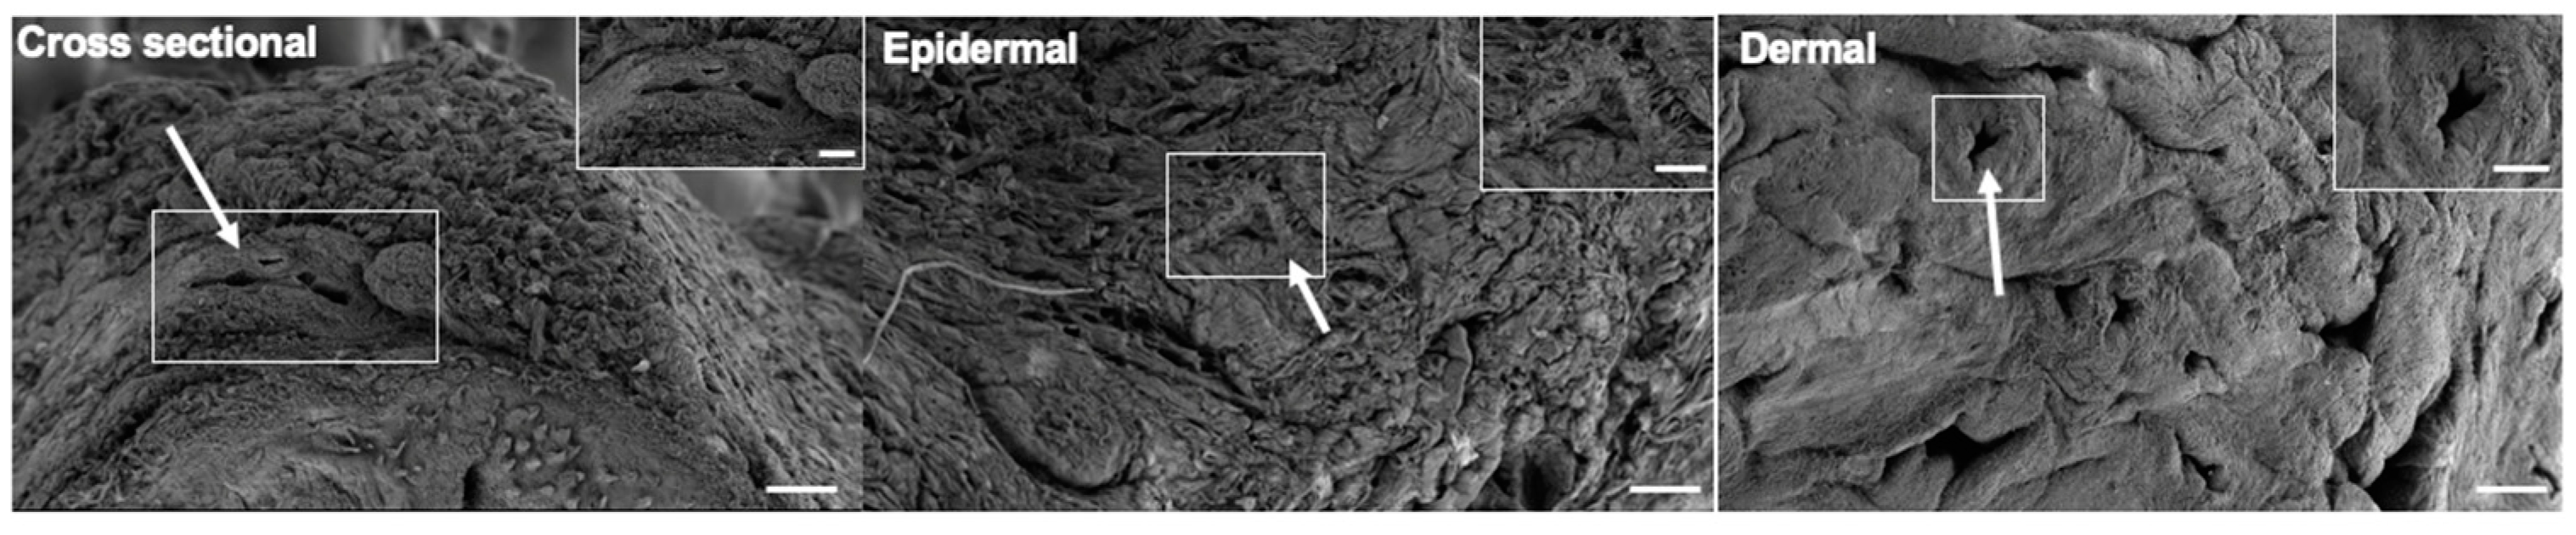

3.3. Microarchitectural and Mechanical Characteristics of Decellularized Facial Grafts